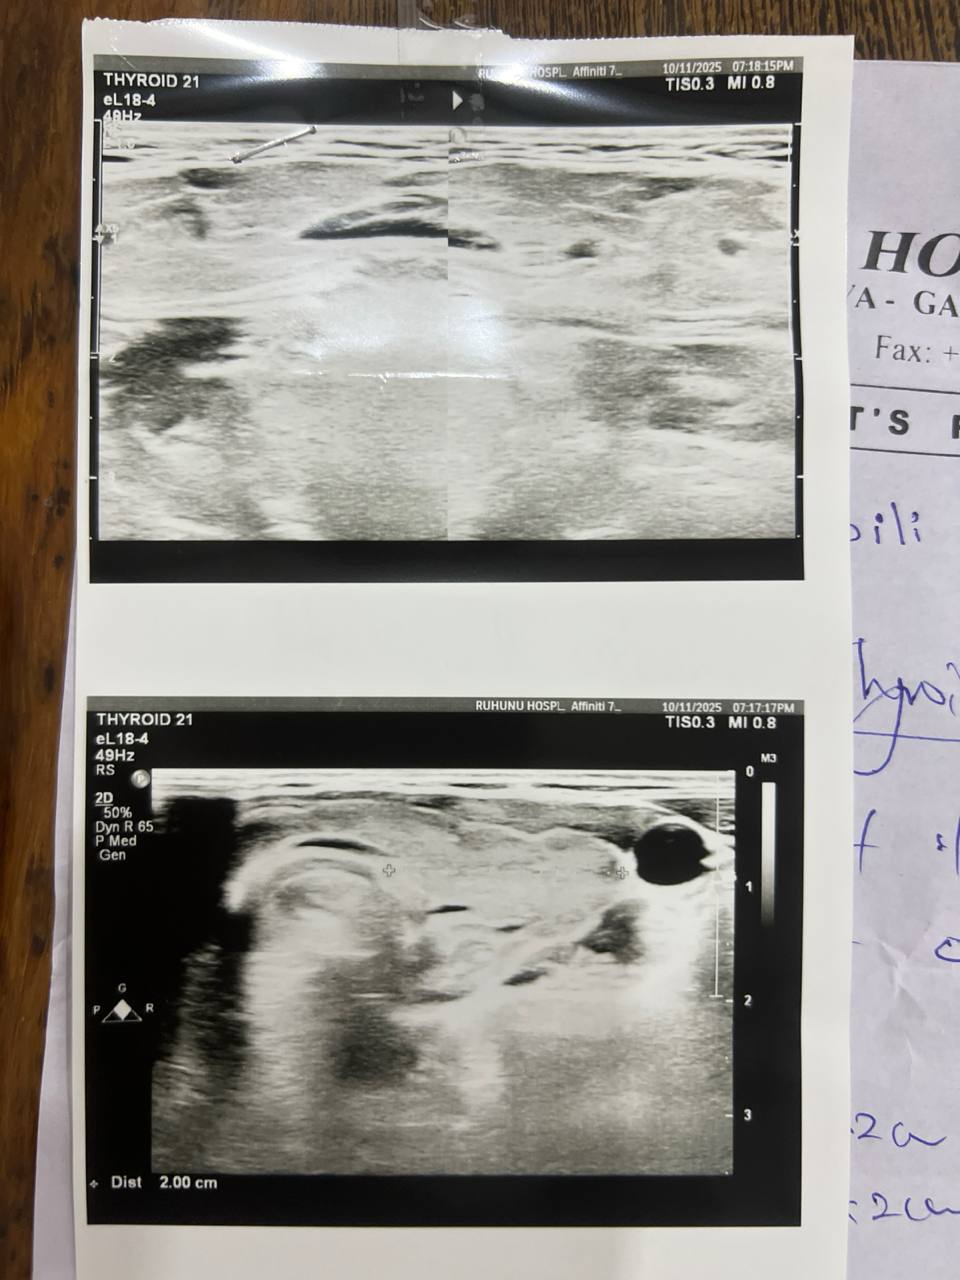

Недавно я сделала УЗИ щитовидной железы:

Незначительное увеличение правой доли щитовидной железы.

Правая доля: 5 см × 1,4 см × 2,2 см

Левая доля: 3,6 см × 0,8 см × 2 см

Очаговых узлов и зоба нет.

Узи расшифровал обычный врач не эндокринолог, вы разбраетесь в снимках? Скажите, подалуйста, на них соответствует картина действительности 65985464.jpg

| Vitaly, здравствуйте! Можете не сомневаться в точности диагноза аутоиммунного тиреоидита, он подтверждается у вас всеми признаками: УЗИ картиной, повышенным титром антител против щитовидной железы, наличием гипофункции - гипотиреоза. Когда начнете лечение гипотиреоза, нужен контроль ТТГ и Т4св через 2-3 мес. для коррекции дозы. Когда доза будет подобрана правильно, можно будет контролировать только ТТГ (TSH) 1 раз в 6 мес. Контролировать и вообще проверять в дальнейшем антитела не требуется, особенно TSH receptor antibodies У вас есть недостаточность витамина Д и железодефицит, рекомендую их устранить приемом витамина Д (в зависимости от веса, не менее 5-7000 IU витамина Д в сутки на 2 мес, затем перейти на поддерживающие дозы - 2000 -2500 IU длительно). И также нужен препарат железа. Контроль ферритина через 1,5-2 мес (цель - выше 50-60). Контроль витамина Д не нужен, анализ не является достоверно точным. Вы можете совместно принимать и левотироксин (гормон), и витамин Д, железо, селен, омега, но не комбинировать одновременно данные БАДы с тироксином (он отдельно принимается, строго натощак утром). Магний можно пропить позже, по окончании приема железа, они мешают усвоению друг друга. Кальций у вас в норме. Изолированное повышение MPV само по себе ни о чем не говорит, если остальные индексы тромбоцитов в норме.